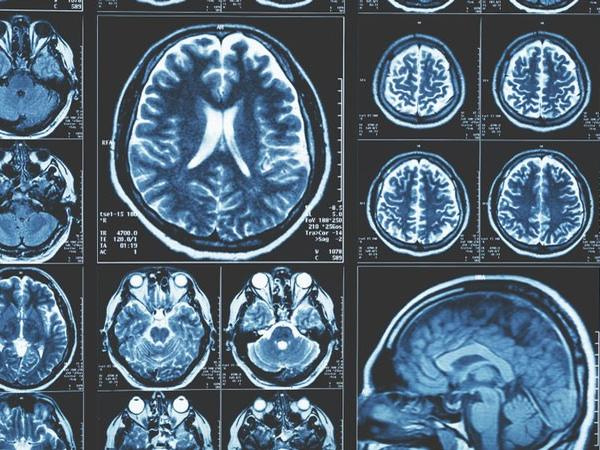

پردازش و آنالیز تصاویر پزشکی، گامی در جهت کیفیت تشخیص

دنیای مدرن امروز این امکان را فراهم آورده تا تصاویر به صورت دیجیتال دریافت و ذخیره شوند. برای بدست آوردن نتایج بهتر گاهی لازم است تا بر روی این تصاویر تغییراتی صورت گیرد این تغییرات سه هدف عمده را دنبال می کنند: پردازش، آنالیز و درک تصویر. به همین دلیل سیستم های کامپیوتری پردازش تصویر بوجود آمده است تا با سرعت و دقت بهتر بتوان این اعمال را انجام داد. در این سیستم ها 4 فرایند عمده اتفاق می افتد: پیش پردازش، ارتقاء کیفیت تصویر، تبدیل تصاویر و طبقه بندی و آنالیز تصاویر. در این روش ها با استفاده از علم ریاضیات قواعدی برای شبیه سازی المان های بینائی انسان توسط کامپیوتر ایجاد شده است و یک جنبه آنالیز تصاویر است که برای منظورهای خاصی کاربرد دارد. دید کامپیوتری (Computer Vision) آنالیز تصویر علمی است که در شاخه های مختلف علم مانند پزشکی، مهندسی، تصویر برداری مولکولی، فضانوردی، امنیتی و …. کاربرد دارد.